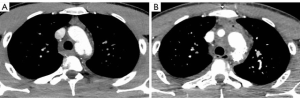

A young 23-year-old man was referred to our hospital for a pseudo-aneurysmal thoracic aortic lesion, caused by trauma sustained during skiing. Immediately after the trauma, the patient was transported to a peripheral hospital because of thoracic and head injuries with loss of consciousness. A full-body CT angiogram was performed and, while brain scans resulted to be negative, the thoraco-abdominal aorta scan showed a lesion of the thoracic aortic isthmus with a semi-circumferential pseudo-aneurysm (Figure 2A).

Two weeks after the operation the patient was discharged in good health. The postoperative period was uneventful and the CT angiogram at postoperative day 10 showed the complete exclusion of the pseudoaneurysm of the aortic isthmus (Figure 2B) and a normal morphology of the Thoraflex hybrid prosthesis and of the re-implanted supra-aortic trunks (Figure 3).